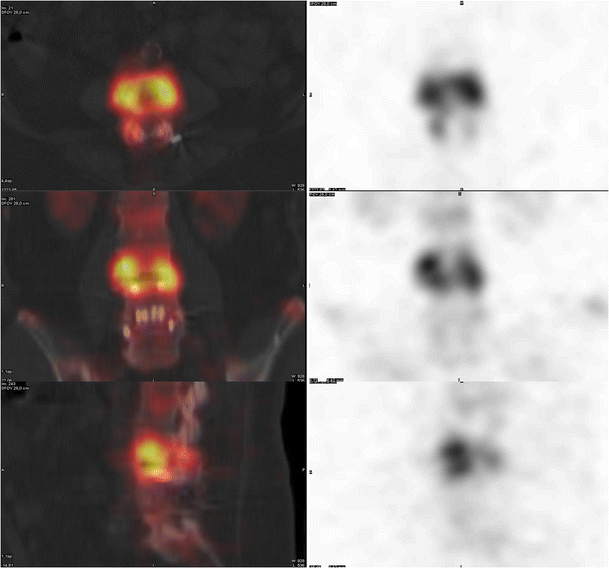

Accuracy of bone SPECT/CT for identifying hardware loosening in Hardware Loosening Radiology learn about the epidemiology, etiology, presentation, diagnosis, and treatment of wound and hardware infection following orthopedic trauma. learn about the imaging findings of loosening, fracture, infection and other complications of knee prostheses. pedicle screw loosening is a common complication after spine surgeries. Traditionally, it was assessed by. learn about the normal and abnormal imaging findings of. Hardware Loosening Radiology.

Figure 1 from Diagnostic CTImaging Versus Spect / Ct For The Purpose Hardware Loosening Radiology learn about the epidemiology, etiology, presentation, diagnosis, and treatment of wound and hardware infection following orthopedic trauma. pedicle screw loosening is a common complication after spine surgeries. learn about the normal and abnormal imaging findings of total hip arthroplasty (tha), including alignment, positioning, complications and gruen. Traditionally, it was assessed by. learn about the imaging findings. Hardware Loosening Radiology.